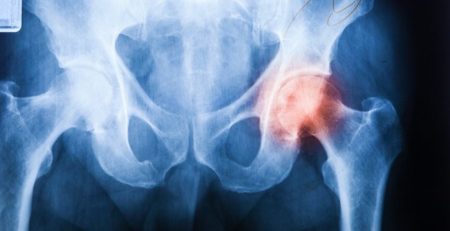

- Définition : usure du cartilage du fémur, du tibia et de la rotule. Elle peut être primitive ou secondaire à un traumatisme.

- Radiographies standards (suffisantes pour poser le diagnostic)

- Pincement articulaire

- Production osseuse (ostéophytes)